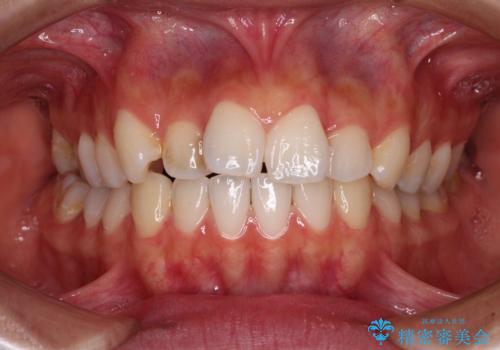

- 【モニター】とがった口元を抜歯して改善 ワイヤー装置の矯正治療- 担当医 藤巻太一朗